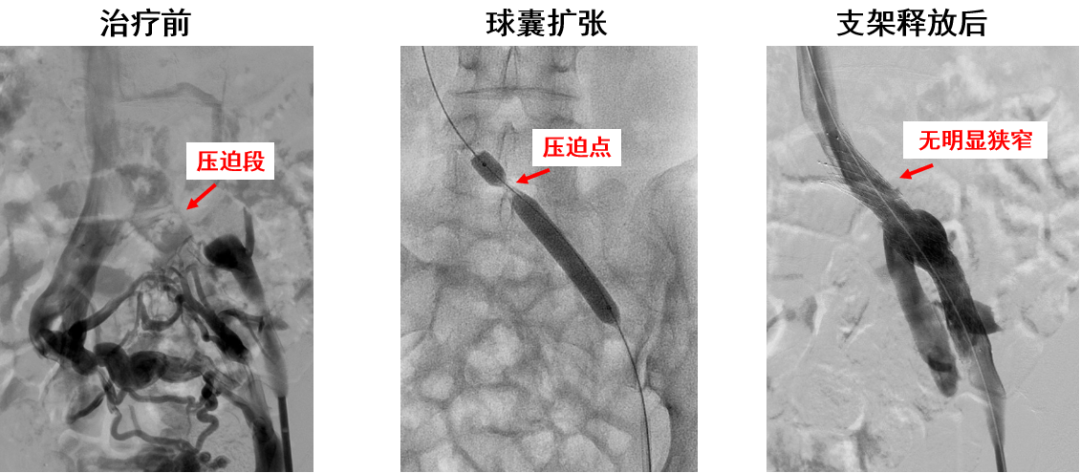

产品E:病例二(多处受压)

产品E:病例三(径向支撑力不足?)

近心端斜口,防对侧血栓形成

有较强的径向支撑力

柔顺性良好

显影性能较好,定位精准

锥形支架设计,贴合血管解剖结构和形态